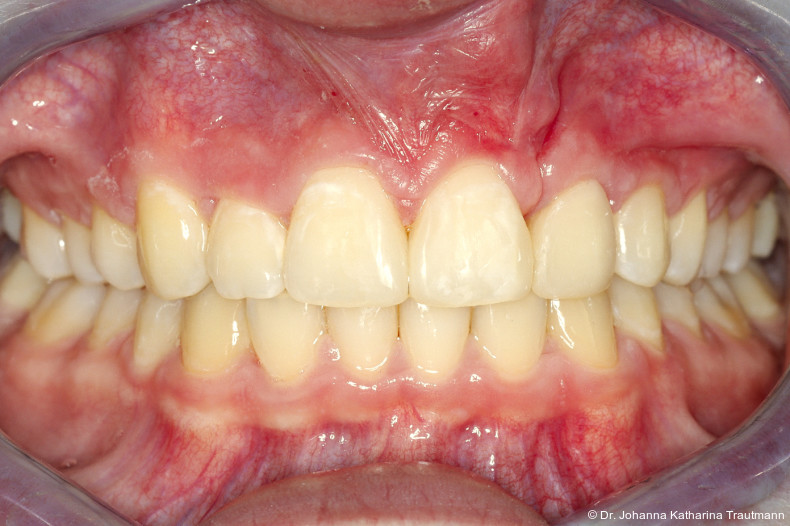

Längere Retentionszeiten ohne odontoplastischen Umbau können das Risiko eines Rezidivs des Zahnes 22 erhöhen. Dennoch ist häufig eine Abheilphase nach der Multibrackettherapie erforderlich, da sich gingivale Entzündungen oft erst nach ein bis drei Monaten vollständig zurückbilden.19–21 Um diesen Zeitraum zu überbrücken wurde an 22 die Kunststoffbasis der DVP (Doppel vorschubplatte) zur Retention sowohl mesial als auch distal extendiert. Schließlich wurden die Zähne 11, 21 und 22 kompositrestaurativ angeglichen, wodurch ein sehr gutes ästhetisches Ergebnis erzielt wer den konnte. Aufbauten mit Komposit bieten eine gute Möglichkeit, bei maximaler Schonung der Zahnhartsubstanz hypoplastische Zähne langfristig zu versorgen, und zeigten in ZehnJahresFollowups hohe Überlebensraten. Entscheidend ist hierbei eine ausgeglichene okklusale Lastverteilung, die mit hilfe einer physiologischen Frontzahnabstützung und gesicherten Okklusion durch die kieferorthopädische Vorbehandlung erreicht werden kann.22

Zur objektiven Quantifizierung des Behand lungsergebnisses wurde der Peer Assess ment Rating(PAR)Index erhoben.23 Im vorliegenden Fall konnte der PAR-Wert von 25 auf zwei reduziert werden, was einer Verbes serung von 92 Prozent entspricht und als hoch wertiges okklusales Ergebnis einzustufen ist.24 Zur Vorhersage der Langzeitstabilität bei Spalterkrankungen lässt sich dieser Fall in die Gruppe 1 des GOSLON Yardstick Index ein ordnen. Dieser sagt eine exzellente Langzeitstabilität vorher.25 Auch der Patient zeigte sich mit dem Ergebnis sehr zufrieden. Während der anderthalbjährigen Retentionsphase erfolgte zusätzlich eine ästhetische Nasenkorrektur zur Aufrichtung des linken Nasenflügels, wodurch neben der dentalen auch die extraorale Rehabilitation erfolgreich abgeschlossen werden konnte.